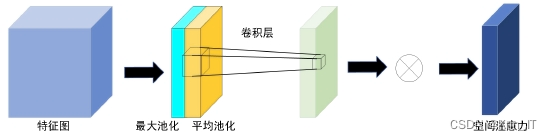

空间注意力机制(SAM)通过对输入特征图进行最大池化和平均池化操作,随后进行卷积处理,生成新的权值,从而获得更具代表性的特征。这一过程允许模型关注输入特征图中的重要区域。通道注意力机制(CAM)则通过分别对输入特征图进行最大池化和平均池化处理,然后利用共享权值生成新的特征,强化了模型对特征通道的关注能力。此外,卷积块注意力机制(CBAM)将空间注意力机制和通道注意力机制相结合,先对特征图进行空间注意力提取,再进行通道注意力处理,最终输出新的特征图。通过这些注意力机制的引入,网络能够更有效地提取和利用关键特征,显著提升目标检测的性能。